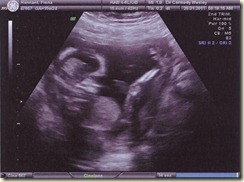

Now on a lighter note below is the 12 week Ultrasound picture and the 3D Ultrasound picture.

The top picture you can see the sonographer measuring the nuchal sack of the baby. This is part of the test for down syndrome (which has very long odds now of some 1 in 3522).